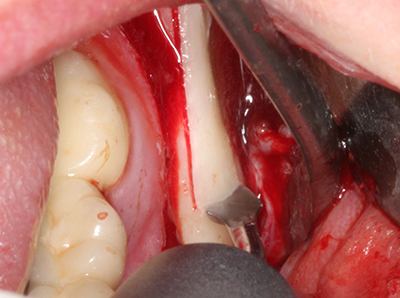

Sollen chirurgische Eingriffe mit unmittelbarer Knochenbeziehung an empfindlichen Strukturen wie Blutgefäßen oder Nerven erfolgen, so bergen rotierende Instrumente ein erhebliches Potential an iatrogener Schädigung. Gerade bei Nervdarstellungen nach iatrogener Schädigung, oder aber im Zuge einer Nervlateralisation für resektive und rekonstruktive Eingriffe oder Implantatinsertionen können piezoelektronische Geräte hilfreich sein Knochendeckel zu präparieren und nervnahe Hartgewebsanteile zu entfernen (Abb. 17-20). Ein leichter Kontakt des Nervstrangs zur Piezospitze bleibt dabei in der Regel folgenlos – allerdings kann eine unvorsichtige Vorgehensweise mit sägeartigen Bewegungen bzw. Ansätzen bei noch vorhandener knöcherner Unterlage durchaus temporäre oder aber auch permanente Nervschädigungen verursachen. Das Risiko einer solchen Schädigung wird jedoch als wesentliche geringer eingeschätzt als unter Anwendung von Säge- oder Fräsinstrumenten (Pereira, Gealh et al. 2014).

Abb. 20: Der entnommene Knochendeckel wird readaptiert und durch eine Osteosyntheseschraube (KLS Martin, Tuttlingen) fixiert.